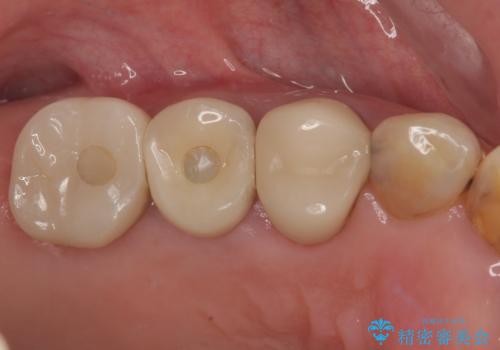

破折して抜歯となった奥歯 抜歯即時埋入・即時荷重インプラントによる補綴治療

- 奥歯の歯茎が腫れているとのことで来院された患者様です。

奥歯の歯根が破折している可能性が高く、破折している場合には抜歯となるため、本当に破折しているのか確認をしてほしいとのことでした。

歯肉を開いて確認をしたところ、著しく骨欠損しており、目視でも歯根破折が確認されました。

3つある歯根の内、1つのみに骨欠損がある状態で、インプラント埋入に十分な骨の状態でした。

抜歯即時埋入・即時荷重の適応と判断されたため、インプラントによる補綴治療を行うこととしました。